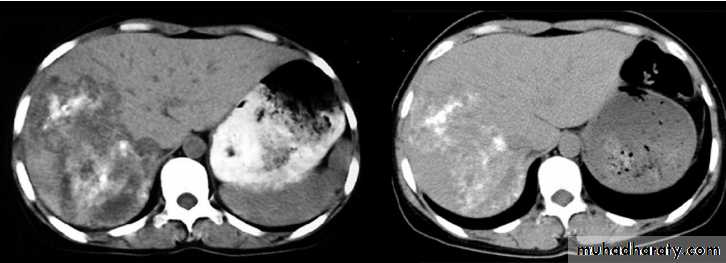

Computed tomography scan of the liver showing a large irregular AE lesion in the right lobe containing scattered

calcifications and liquefactions (left panel). After five years of treatment with albendazole, the lesion had not changed in

size but the areas of calcification had increased and those of liquefaction had decreased (right panel)